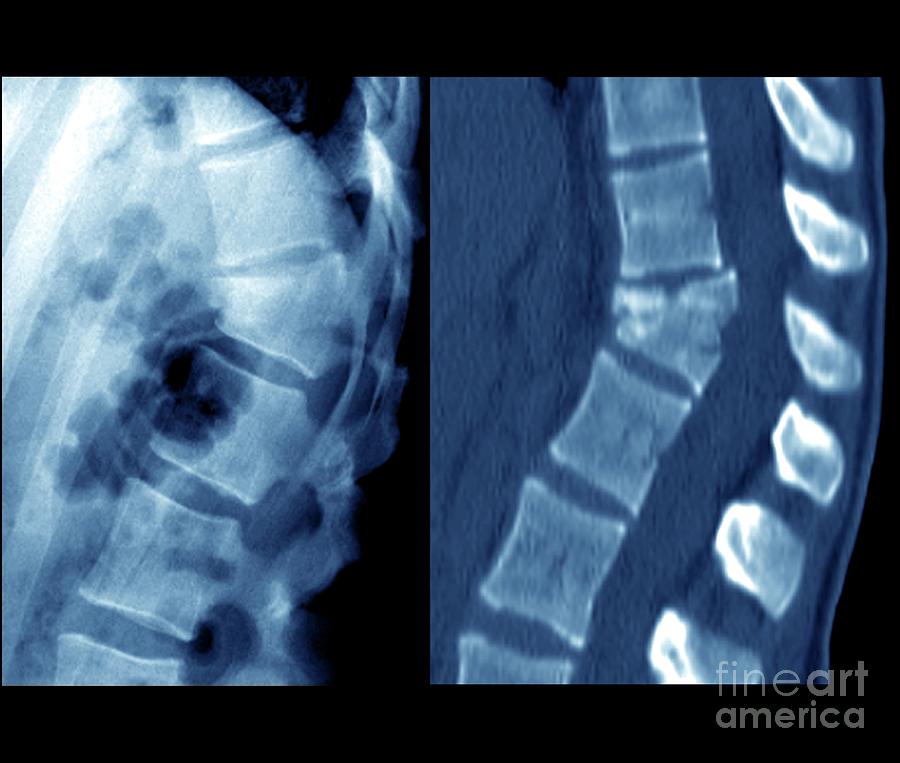

Fractured spine

Fractured spine 140 фотографий